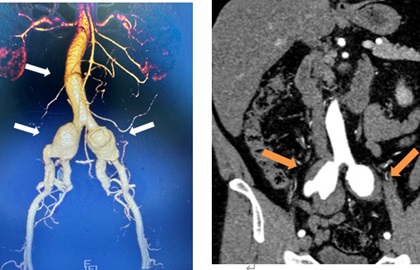

- 一连串,没有症状,体检意外发现!我院医生腹内“拆弹”!